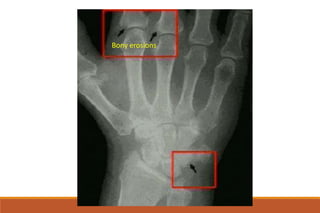

RHEUMATOID ARTHRITIS

X-rays

◦ The earliest changes occur in the wrist or feet and consist of soft

tissue swelling and juxta-articular demineralization.

◦ Later, diagnostic changes consisting of joint space narrowing and

erosions develop. The erosions are first seen at the ulnar styloid

and at the juxta-articular margin, where the bony surface is not

protected by cartilage.

Juxta-articular osteoporosis

Bony erosions